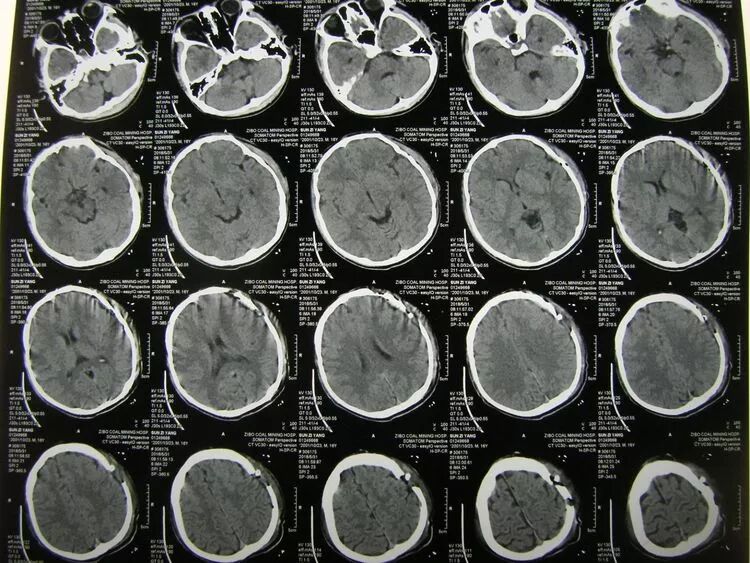

术后1天CT复查,血肿清除满意,未见迟发出血,患儿神志清醒。

术后2周CT复查,颅内未见迟发病灶,创口愈合良好,患儿己下床活动,拆线后出院。